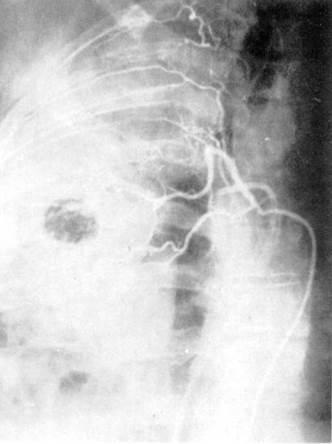

Бронхиальную артериографию

в регионах выше и ниже выявляемых анастомозов двух систем кровообращения легких. Рис. 6.

Ангиопульмонография.

а — артериальная фаза; б — капиллярная фаза; в — венозная фаза.

Рис.

7.

Селективная ангиография бронхиальных артерий.

При анализе ангиопульмонограмм

обращают внимание на пофазовое

продвижение контрастного вещества по различным регионам легкого: легочной артерии, капиллярного русла, венозной системы малого круга кровообращения (рис. 6).

По комбинации ангиографических

признаков представляется возможным охарактеризовать вид и распространенность патологического процесса (при двухпроекционной сериографии

— посегментарно)

в легком, при этом обращается внимание на наличие деформации сосудов, смещение, контуры, разреженность сосудистого рисунка (рарефикацию),

степень развития сосудов отдельных сегментов, долей, легкого, характер расположения камер сердца, ротацию сердца и др.

При селективной ангиографии бронхиальных артерий катетер вводится в грудную аорту и далее — до устья бронхиальных сосудов; введение контрастного вещества осуществляется с помощью автоматического инъектора.

Сериография,

проводимая, как правило, в переднезадней проекции, может быть дополнена рентгенограммами в боковой или косой проекциях в зависимости от задач исследования (рис. 7).

При анализе бронхиальных ангиограмм

определяются уровень и тип анатомического ветвления сосудов, положение, форма, диаметр, характер контуров сосуда, извитость его и проходимость, характер и уровень окклюзии, степень развития коллатеральных ветвлений и их взаимосвязь с легочной артерией. Учитываются уровни анастомозирования

двух систем кровообращения легких (субсегменты, сегменты, доли или